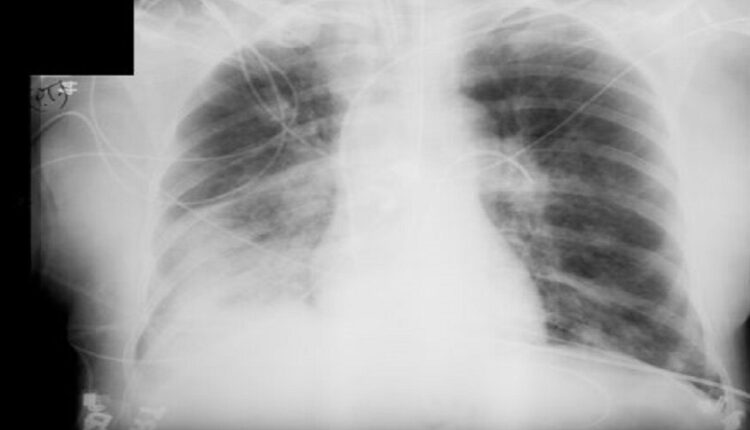

أفادت الدكتورة أوكسانا بلاتونوفا أخصائية الأشعة، أن الأشعة السينية لا تزال أداة تشخيصية مهمة، ولكن لا تزال المخاوف تحيط بها.

وتؤكد بلاتونوفا، أن عدم اكتشاف المرض أخطر بكثير من الخضوع للأشعة السينية، حيث المعدات الحديثة تقلل من المخاطر، كما أن الفحوصات في الوقت المناسب تسمح بالكشف السريع عن الأمراض وبدء العلاج.